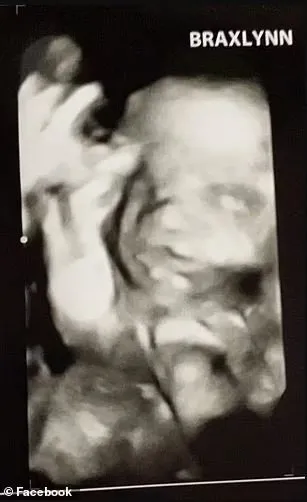

Savcılar, Parker'ın daha önce geçirdiği bir ameliyat nedeni ile çocuk sahibi olamadığını iddia etti. Sevgilisini kaybetmekten korkan kadının hamile taklidi yaptığını belirtti. Parker'ın aylarca hamile gibi gösterdiği sahte ultrason görüntüleri buldu, hatta sahte bebek için Baby Shower partisi düzenlemiş.